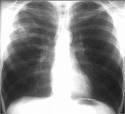

TB can and does affect every organ in the body. We most often associate it with the lungs and this is often the case. A healthy body can wall off the mycobacterium by forming tubercles, hence the name of the disease. A person can live this way for most of one's life without being affected by the latent form of the disease. Should the immune system become compromised, such as with HIV/AIDS, the tubercles give way and the TB takes an active form.